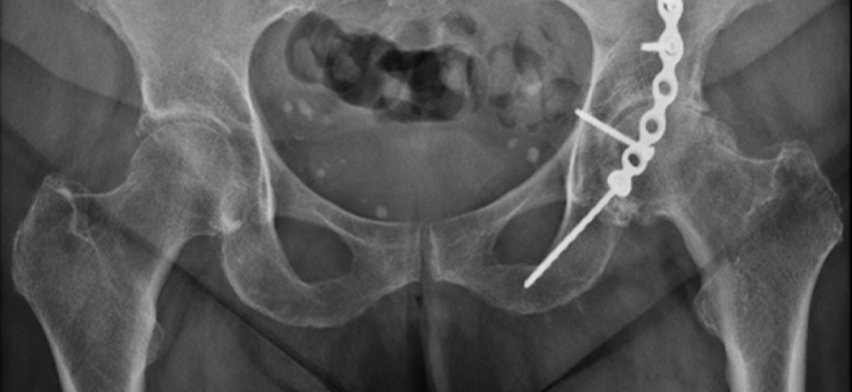

Most displaced or unstable pelvic / acetabular fractures require surgical repair, typically through open reduction and internal fixation (ORIF) using plates, screws, and implants to:

• Restore anatomic alignment

• Rebuild the hip socket stability

• Allow for the best possible functional outcome and reduce arthritis risk.